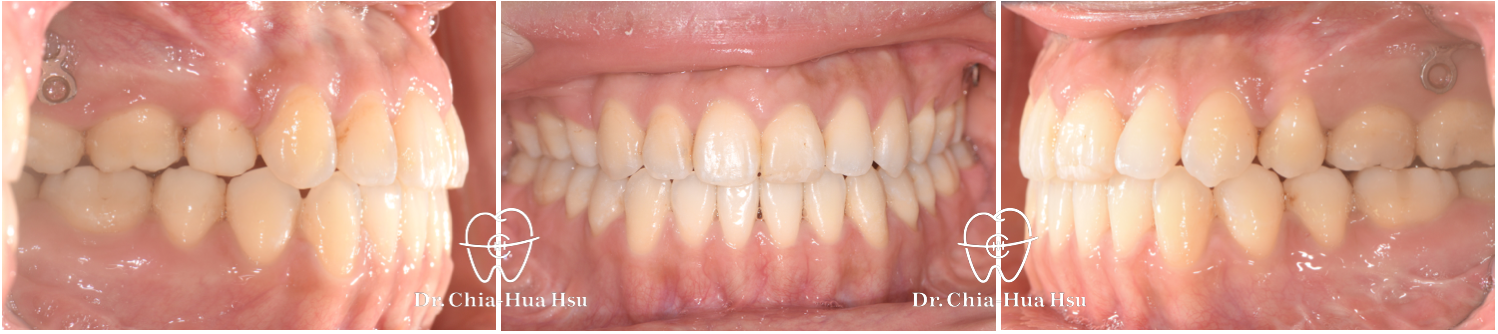

戽斗、前牙錯咬、開咬

成⼈矯正 | ⾦屬矯正 | 正顎⼿術

治療前

治療後